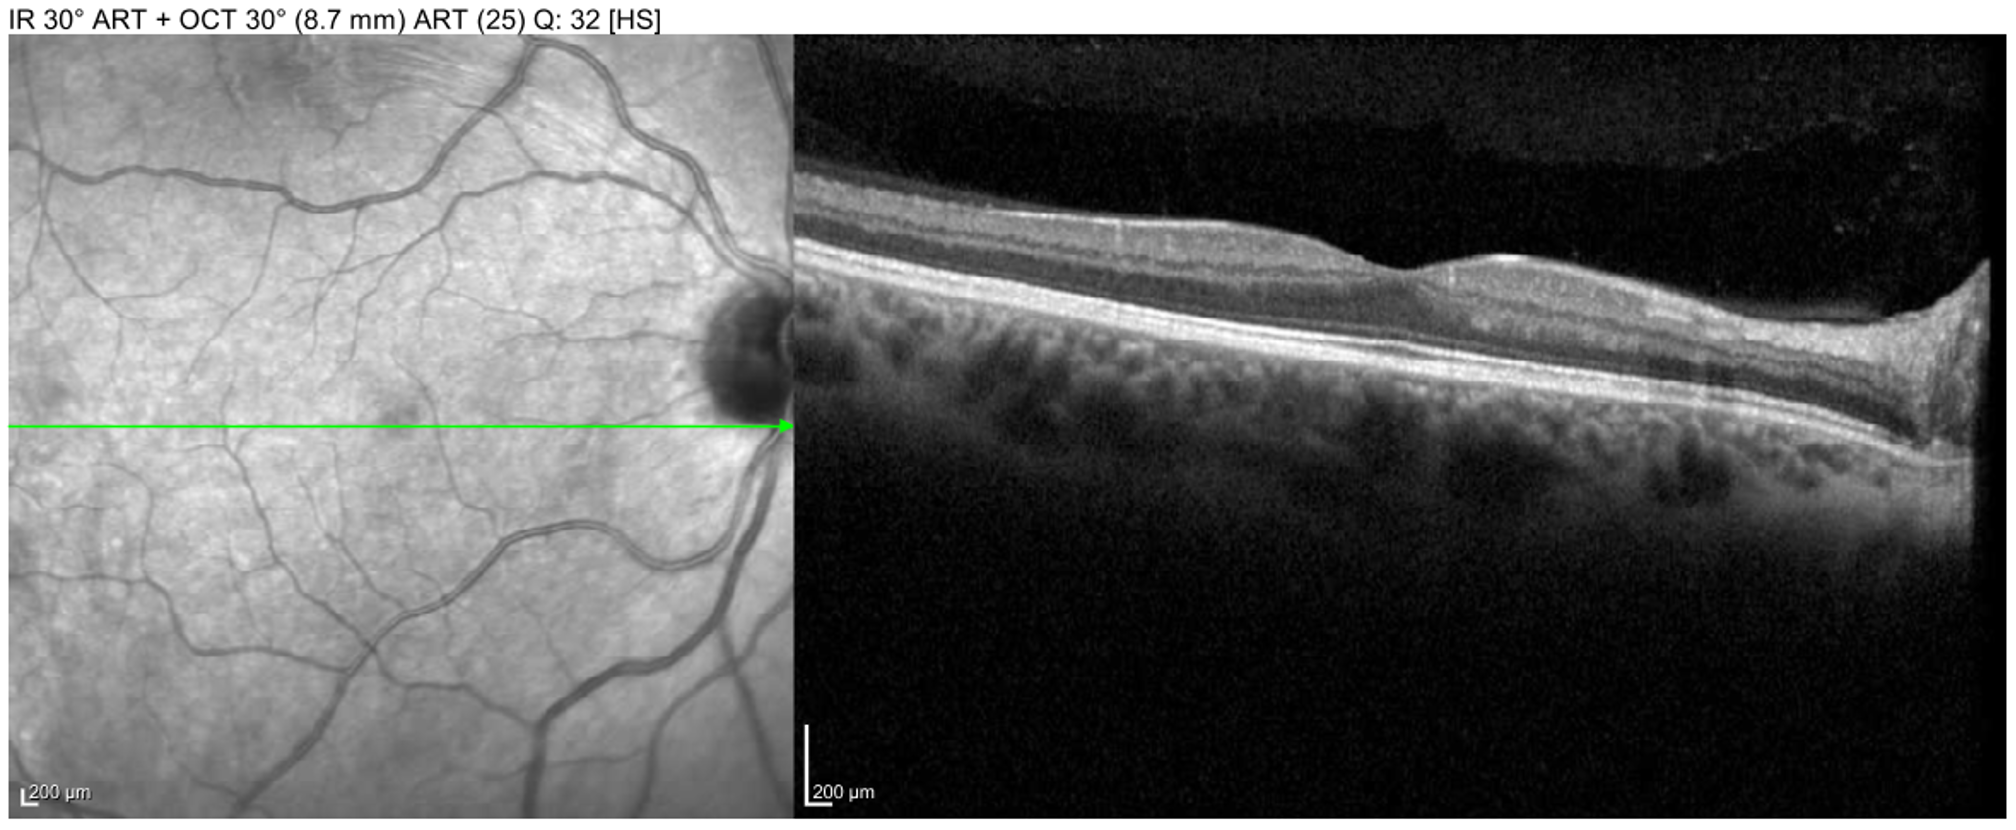

• OCT Macula (Figures 5 and 6):

• OD: one superior area of BRAO visible on near infrared

• OS: large superior BRAO involving the macula

Macula OCT of the right eye showing a small superior BRAO visible on near-infrared en-face image.

Enlarge Download

Figure 5. Macula OCT of the right eye showing a small superior BRAO visible on near-infrared en-face image.

Macula OCT of the left eye showing large BRAO in the macula with inner-retinal edema and hyperreflectivity.

Figure 6. Macula OCT of the left eye showing large BRAO in the macula with inner-retinal edema and hyperreflectivity.